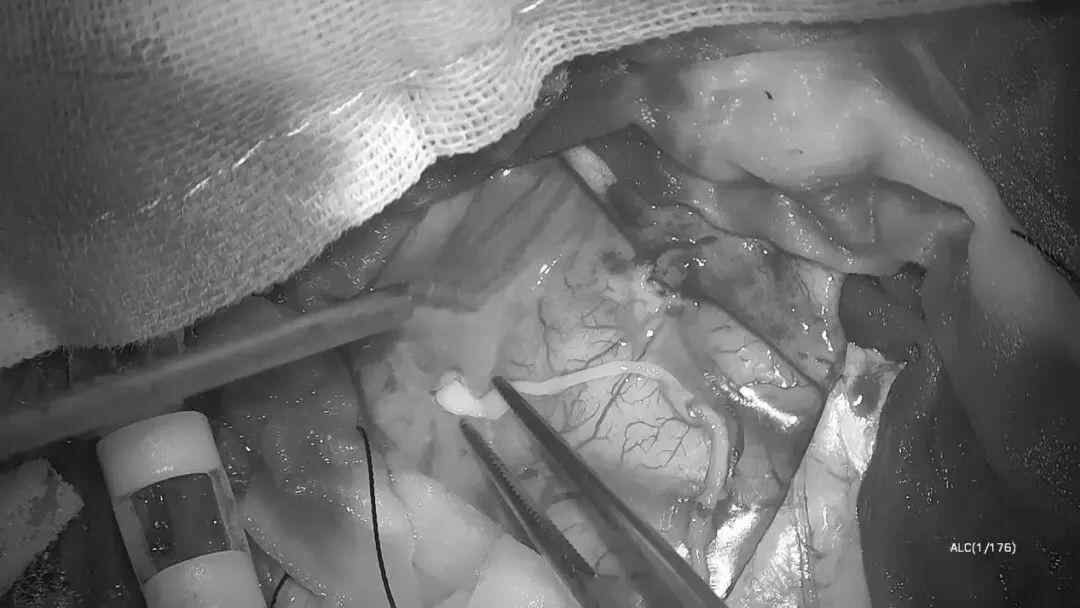

手术当天,医护团队先在全麻状态下完成开颅。当暴露病灶区域时,麻醉科医生逐步调整用药,将林浩从麻醉中唤醒,“能听见我说话吗?试着睁睁眼。”林浩根据指令吐舌、握拳、回答简单问题……通过实时互动,张旭标精准定位功能区边界,并成功捕获一条约10厘米长、仍在蠕动的裂头蚴。

医生边聊天边在脑内捉虫

活虫长达10厘米